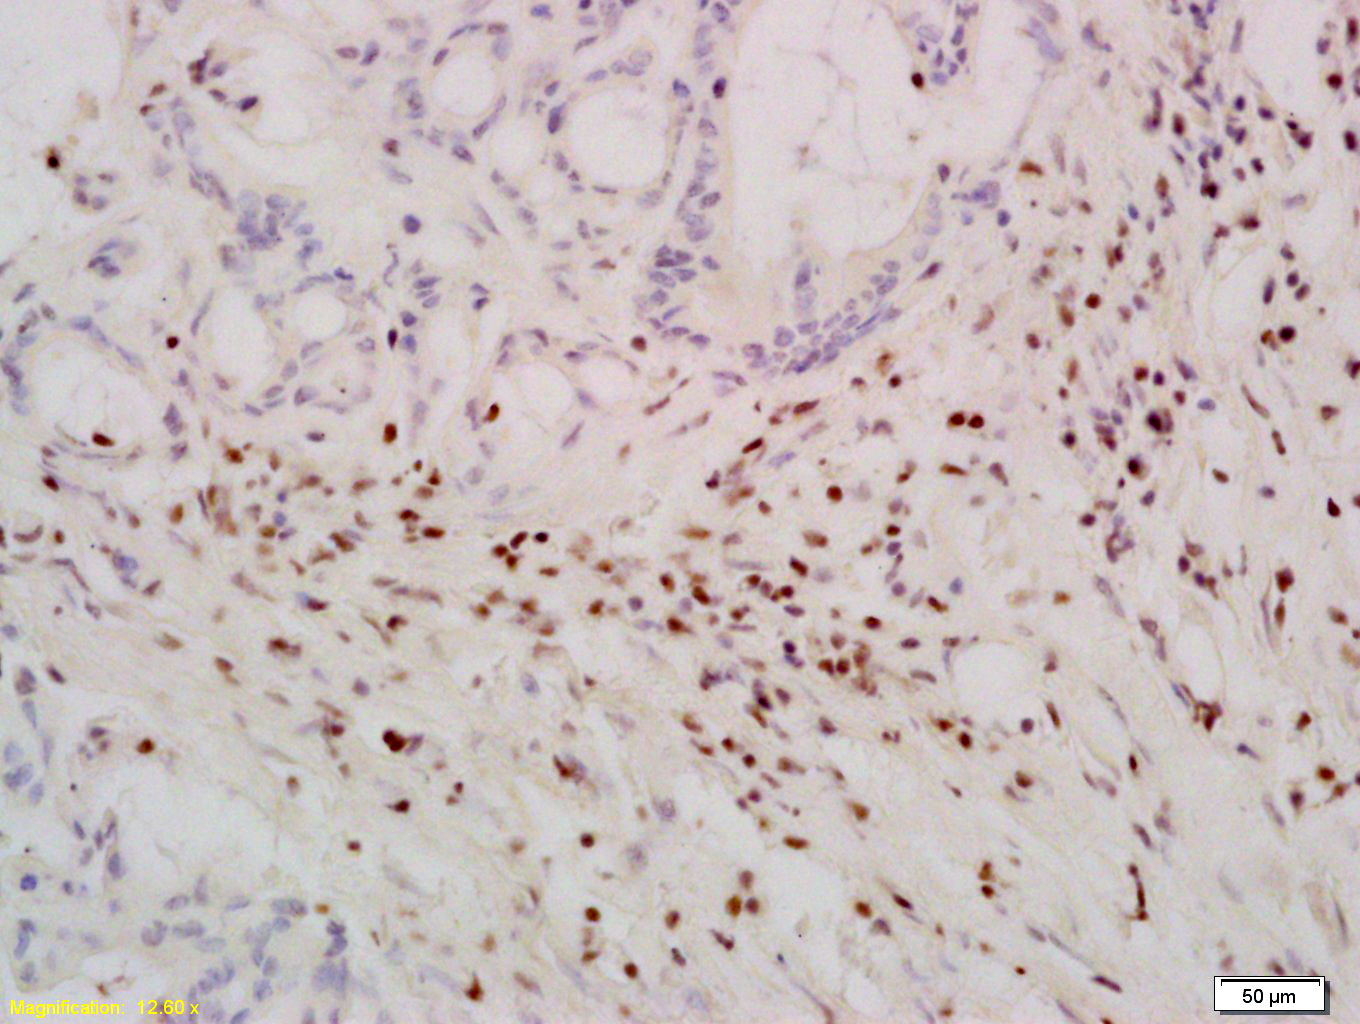

Paraformaldehyde-fixed, paraffin embedded Rat Liver; Antigen retrieval by boiling in sodium citrate buffer (pH6.0) for 15min; Block endogenous peroxidase by 3% hydrogen peroxide for 20 minutes; Blocking buffer (normal goat serum) at 37°C for 30min; Antibody incubation with TERT Polyclonal Antibody, Unconjugated (bs-0233R) at 1:400 overnight at 4°C, DAB staining.